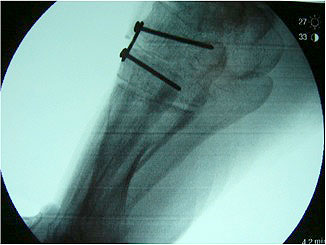

Stadium III – partielle Rückfuß-Arthrodesen

- In-situ / korrigierende USG-Arthrodese

Im Stadium III der Tibialis posterior Sehneninsuffizienz bei fixierter Deformität und/oder erheblich eingeschränkter Inversion im USG aber stabilen und flexiblen Chopart-Gelenk und weniger als 10° fixierter Vorfußsupination eine in-situ oder leicht korrigierende USG-Arthrodese indiziert. Der Vorteil einer isolierten USG-Arthrodese gegenüber einer Triple- oder Double-Arthrodese ist die verbleibende, funktionell wichtige Beweglichkeit in der Chopart-Gelenkreihe. Um einem persistierenden fibulocalcanearem Impingement sicher vorzubeugen, sollte die USG-Arthrodese in maximal 5° Valgus- oder sogar Neutralposition erfolgen. Zur Prophylaxe eines Rezidivs wird die USG-Arthrodese zudem häufig mit einer medialisierende Tuber calcanei Osteotomie und / oder einem FDL-Transfer kombiniert (Abb. 12).